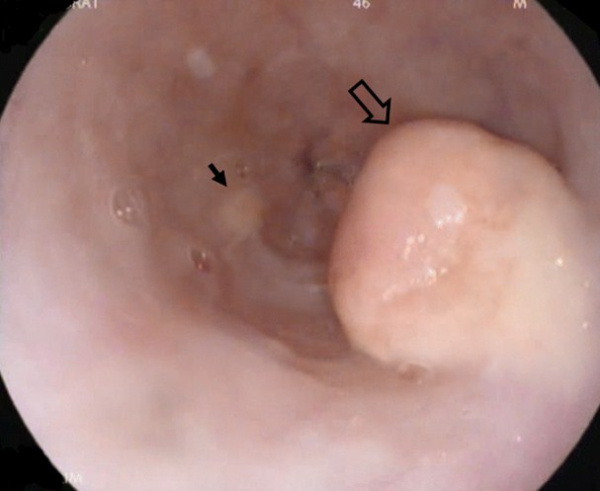

(Справа) На УЗИ в сагиттальной плоскости у пациента с псевдомиксомой брюшины визуализируется вторичный очаг возле печени. Несмотря на то, что очаги выглядят кистозными на КТ, на УЗИ они определяются как эхогенные образования солидного характера.